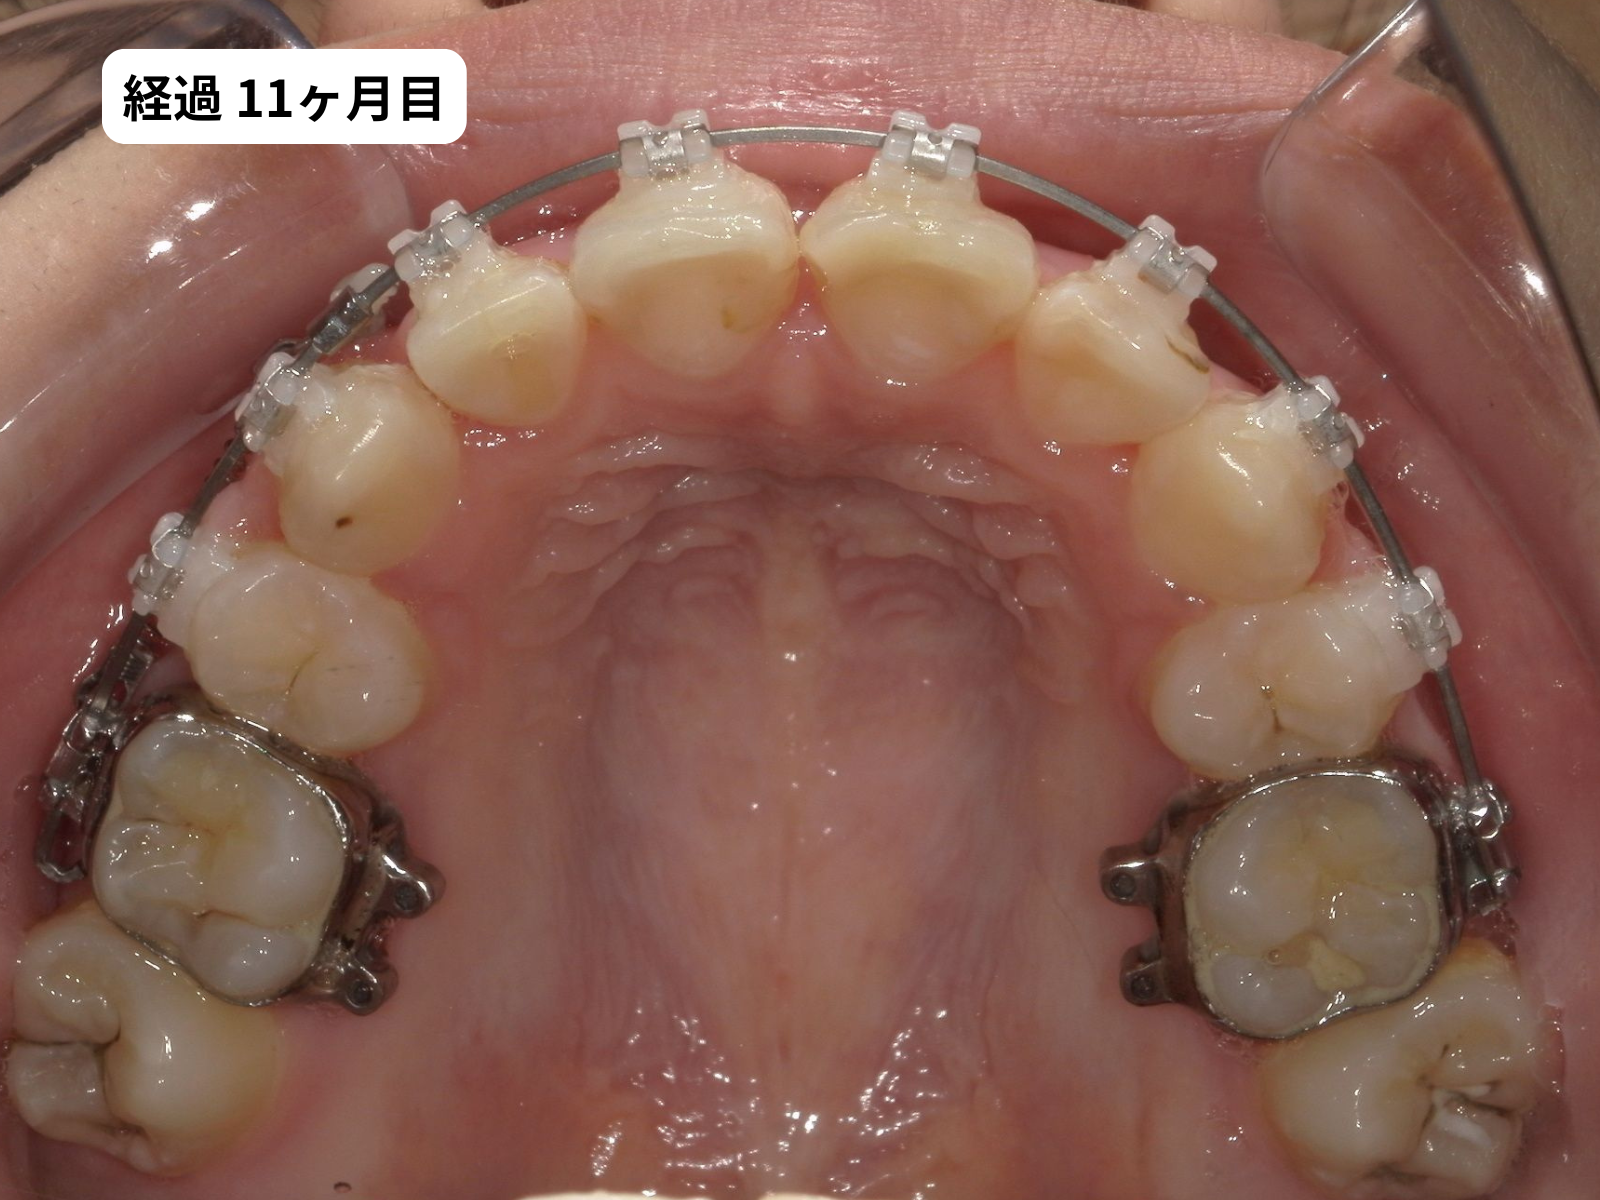

装置装着から1年2ヶ月、毎月の経過

装置をつけた後、上の歯の噛み合わせ面の写真を毎月記録しました。下のスライダーで、月ごとに歯がどう動いていったかをご覧いただけます。

毎月の写真で歯がスムーズに動いているのがわかります。これは 軽い力(約50g)でゆっくり動かす、毎回の来院で移動距離を確認する、この2つを積み重ねた結果です。